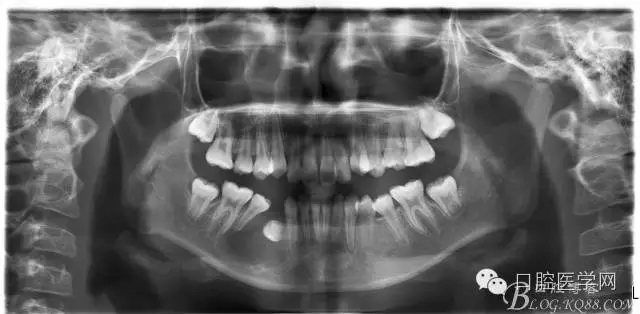

查:右側(cè)第二前磨牙第一乳磨牙恒尖牙頰側(cè)前庭溝隆起,捫有乒乓球感。曲斷及CT示:右側(cè)第二前磨牙第一乳磨牙恒尖牙根尖區(qū)有一囊腫,頰舌側(cè)骨板極薄,牙根無吸收,第二前磨牙牙根位于囊腫中,第一雙尖牙牙冠遠(yuǎn)中水平向阻生,牙冠位于囊腫中。經(jīng)協(xié)議:手術(shù)摘除創(chuàng)傷大,同意開創(chuàng)引流保守治療。

否認(rèn)手術(shù)禁忌癥及過敏史。消毒,局麻下鋪巾,拔出第一乳磨牙,有囊液溢出,擴(kuò)大開放引流孔,取部分囊壁送病理,生理鹽水沖洗,置引流管縫合固定。病理報告:囊腫。八月后局麻拔除第一雙尖牙刮凈剩余變小的囊壁。

術(shù)后一個月 三個月 五個月 八個月 拔除第一雙尖牙后 曲斷片: